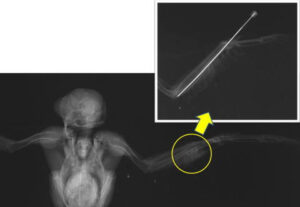

整復オペ Before & After

レントゲン検査の結果、左翼の「尺骨」という骨に、骨折が認められました。体重がわずか180gしかない非常に小さな体のため、あまり重い固定器具を使うことはできません。今回は脊髄麻酔用の特殊な注射針を、骨を固定するピンに改造して利用しました。

接合完了!

ピンを入れた骨が完全に付くまで、翼はテーピングでしっかりと固定します。しばらくは狭いケージの中で我慢の日々を過ごしてもらいました。オペを行ってから18日後、レントゲン検査の結果、骨折していた骨が癒合していることが確認されました。もう固定具は必要ありません。ピンを抜き、飛翔訓練の始まりです。